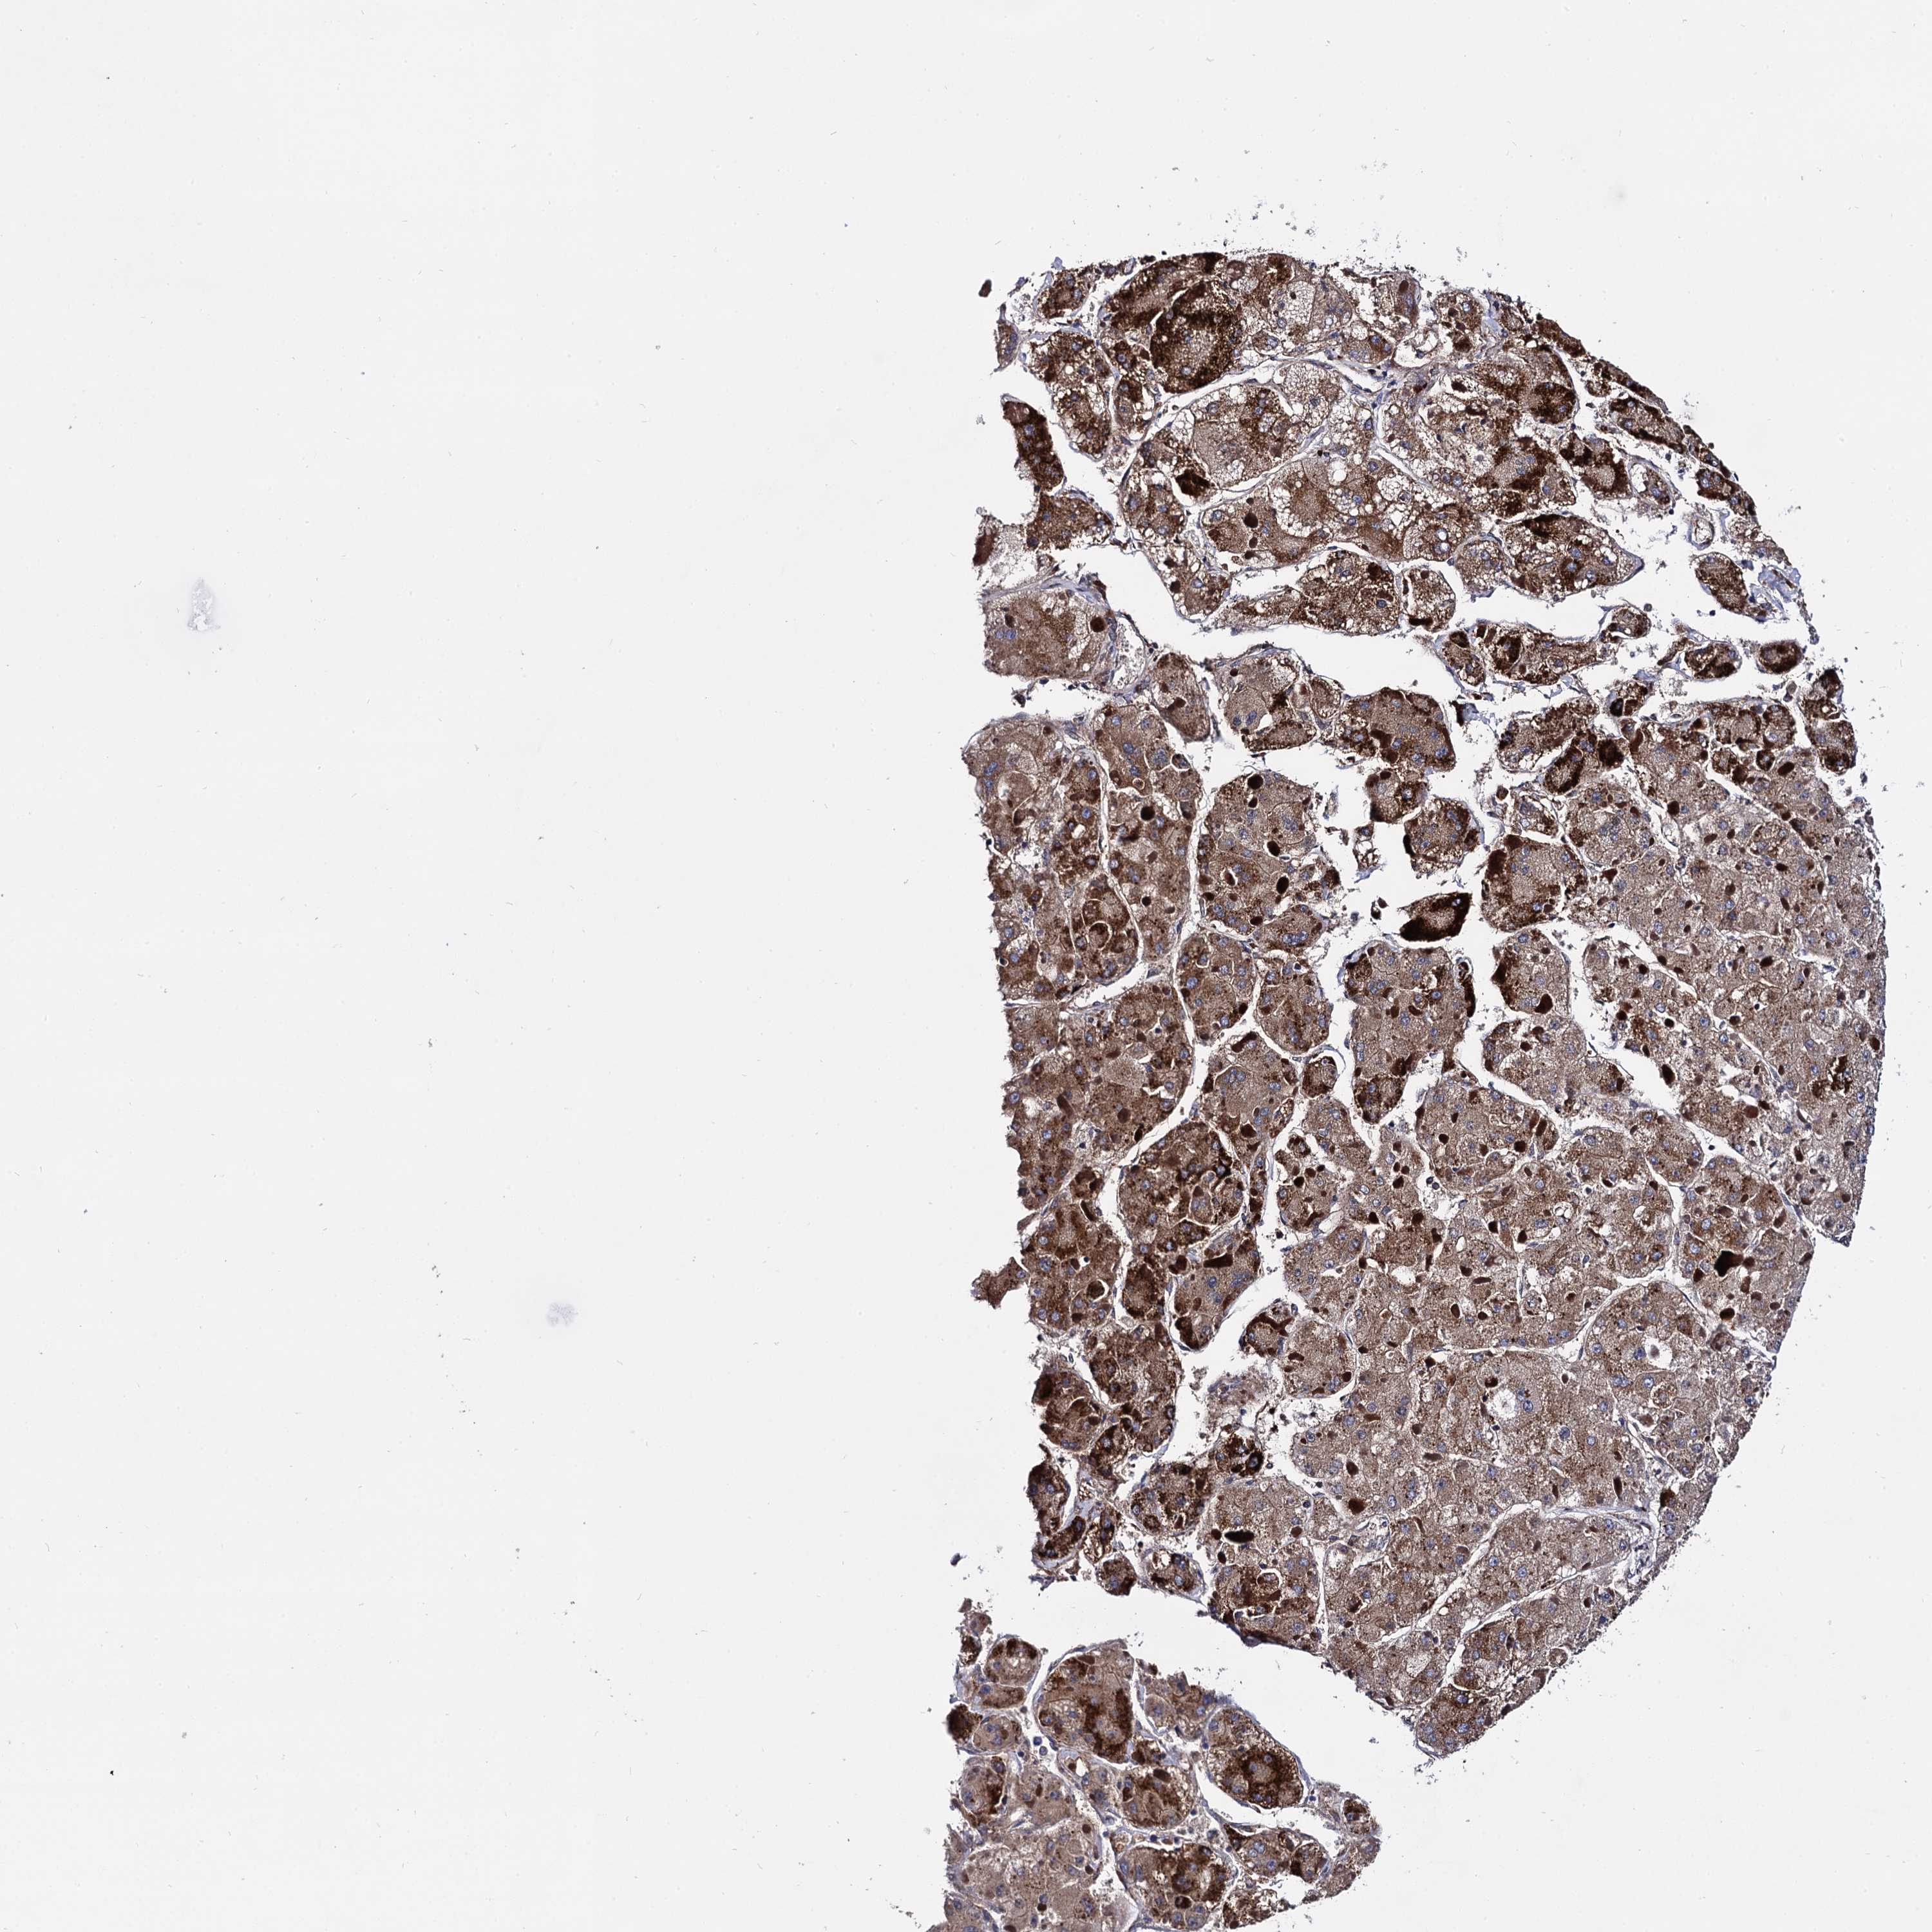

LIVER CANCER - Protein expressioni

A mouse-over function shows sample information and annotation data. Click on an image to view it in a full screen mode. Samples can be filtered based on level of antibody staining by selecting one or several of the following categories: high, medium, low and not detected. The assay and annotation is described here.

Note that samples used for immunohistochemistry by the Human Protein Atlas do not correspond to samples in the TCGA dataset.

Antibody stainingi

Antibody staining in the annotated cell types in the current human tissue is reported as not detected, low, medium, or high, based on conventional immunohistochemistry profiling in selected tissues. This score is based on the combination of the staining intensity and fraction of stained cells.

Each image is clickable and will lead to virtual microscopy that enables deeper exploration of all samples and also displays staining intensity scores, fraction scores and subcellular localization as well as patient and tissue information for each sample.

Antibody HPA040845

Staining

High

Medium

Low

Not detected

Intensity

Strong

Moderate

Weak

Negative

Quantity

>75%

75%-25%

<25%

None

Location

Nuclear

Cytoplasmic/membranous

Cytoplasmic/membranous,nuclear

Cholangiocarcinoma

Carcinoma, Hepatocellular, NOS